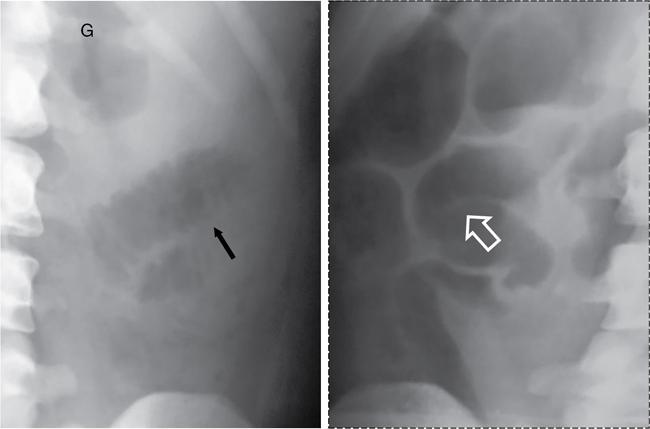

UNDERSTANDING THE ADULT ABDOMINAL RADIOGRAPH: TECHNIQUES AND INTERPRETATION Tanvi Modi Radiography of the abdomen is a common practice for the evaluation of abdominal organs. The anatomy and pathology of digestive, hepatobiliary and genitourinary systems can be assessed using radiographs, either as a stand-alone practice or as a primary imaging modality followed by contrast studies, ultrasound or cross-sectional imaging. In addition, abnormalities of the musculoskeletal or integumentary system can also be deduced on the basis of abdominal radiographs. This chapter intends to give an overview on the techniques and positioning in abdominal radiography as well as interpretation of normal and abnormal features. While superior imaging modalities such as ultrasound, computed tomography (CT), magnetic resonance imaging, capsule endoscopy and the likes have taken over abdominal imaging by and large, radiography still holds a pivotal role in certain situations and conditions, such as: The standard abdominal radiograph is taken in supine position and anteroposterior projection. This is also popularly known as the KUB (kidneys-ureters-bladder) radiograph. Previously, supine as well as erect radiographs were performed in all patients; however, this is not commonly done due to high-radiation dose. For all indications of abdominal radiography, including acute abdomen, supine radiographs are sufficient in terms of radiographic diagnosis, with the exception of perforation for which an erect chest or lateral decubitus radiograph can be performed if there is clinical suspicion. Patient should lie supine on the imaging table with median sagittal plane at right angles to the table and coincident with the midline of the table (Fig. 7.1.1.1). The body is divided into equal right and left halves by the median sagittal which passes through the sagittal suture of the skull. Pelvis should be adjusted so that the anterior superior iliac spines are equidistant from the table top. Gonadal shields, in the case of male patients, should be placed with the upper edge of the shield at the level of pubic symphysis. Although rarely used for female patients, these should be positioned between the anterior superior iliac spines and the pubic symphysis. The centre point of the image receptor should be approximately located at a point 1 cm below the line joining the iliac crests. The X-ray beam should be in a vertical direction, perpendicular to the table top and image receptor at the centre point. Collimation should be such that the soft tissue and subcutaneous region along lateral aspects of the abdominal cavity should be covered within the image. Also, the superior extent involving diaphragm and inferior extent involving the inferior pubic rami is important to look for any lower chest pathologies or any inguinal hernia. 35 × 43 cm (14 × 17 inches) in portrait orientation. On an average, abdominal radiograph exposes a patient to a dose of approximately 1.5 mSv, which is equivalent to 75 chest radiographs or 1/6th dose of a standard CT of the abdomen. The entrance skin dose is approximated to be 4 mGy. At such an effective dose, the additional lifetime risk of fatal cancer is 1 in 30,000. The exposure time is kept short. Patient is asked to exhale completely and hold their breath, with exposure taken at this point of full expiration to ensure imaging of abdominal organs in their natural positions. Modifications of this technique can be made depending on patient habitus and clinical condition. Kilovoltage peak (kVp) should be set to allow adequate visualization of abdominal soft tissue structures as well as semiopaque renal and biliary calculi. Average kVp is set at 70–85 kV. 102 cm (40 inches) Grids are commonly used to reduce scatter radiation. Placement of side marker on the image receptor at the time of radiographic exposure is essential. Bowel pattern depiction should be such that there is minimal lack of sharpness. Standard guidelines for abdominal radiography dictate that the radiograph should extend from the diaphragm up to the level of inferior pubic rami and must include the lateral abdominal wall musculature. The abdomen is divided into four quadrants on the basis of two perpendicular lines (Fig. 7.1.1.7). The vertical line passes through the mid sagittal plane and crosses the umbilicus and symphysis pubis. The horizontal line is a transverse line across the umbilicus at 90 degrees to the vertical line and is situated at the level of L4–L5 intervertebral disc. The quadrants are as follows: Another division system is dividing the abdominopelvic cavity into nine regions using two vertical and two horizontal planes (Fig. 7.1.1.8). The vertical planes, also known as the right and left lateral planes, are parallel to the midsagittal plane between midline and anterosuperior iliac spines on either side. Of the two horizontal planes, the upper transpyloric plane is at the level of lower border of L1 and the lower transtubercular plane is at the level of L5. The nine regions are: On a standard radiograph, the exposure should be such that the stomach, bowel loops, outlines of liver, spleen, kidneys, psoas muscles should be well identified. Also, lumbar transverse processes should be seen. Arch of the pubic symphysis should be visible to evaluate bladder region. A well-centred film without rotation will demonstrate bilaterally symmetrical lower ribs, iliac wings, ischial spines and obturator foramina. Different structures seen on an abdominal radiograph can be classified into five basic densities: Identification of different structures depends on the relative degree of contrast between their densities. The demarcation is clearer in chest and is diminished in abdomen due to relative similar soft tissue density of various structures. On a normal radiograph, relatively large amounts of gas in stomach and colon with minimal small bowel gas can be seen. Further, colonic gas can vary from negligible to extensive, mimicking obstruction pattern; however, usually the gas is enough to delineate colonic haustral pattern. Faecal matter gives a mottled appearance to colonic gas. Short-air fluid levels on an erect radiograph may be seen even in normal cases. The normal appearance of small bowel loops on an abdominal radiograph follows the rule of threes: Stomach is seen in the left upper quadrant and is visualized when distended with air. It is commonly seen extending from T11 to L2 level. Common feature identifying the stomach is the fundal gas which is usually seen as an air fluid level within the gastric lumen. Small bowel loops are distributed to the centre of the abdominal cavity and large bowel loops are peripheral. Duodenum is predominantly situated in right upper quadrant. It extends to left upper quadrant in the region of duodenojejunal flexure. Jejunum occupies the left upper and lower quadrants and is easily identified due to the presence of thick, numerous, closely spaced valvulae conniventes (Fig. 7.1.1.9A). The ileum occupies both lower quadrants and extends into right upper quadrant. Ileum has few and less prominent valvulae as compared to jejunum (Fig. 7.1.1.9B). Ascending and descending colon are retroperitoneal and have relatively fixed positions along lateral aspect of the abdominal cavity on either side. Transverse and sigmoid colon, on the other hand, may have a variable position due to their mobility along mesocolon and redundant pattern. These can be identified with confidence on account of haustrations and faecal matter (Fig. 7.1.1.10). Haustrations are usually well seen in ascending and transverse colon and poorly delineated beyond splenic flexure. Caecum is in the right lower quadrant, though it may be mobile or pulled up. Rectal gas is usually seen in the midline at the level of pelvis and its presence rules out large bowel obstruction. All these positions may vary due to anatomical conditions such as malrotation or pathological conditions, for example volvulus. Liver, spleen and renal outlines cannot be completely traced with precision due to the overlap by bowel loops. On a frontal projection, the liver appears as a triangular structure occupying right and left hypochondrium and epigastric region. Occasionally, the right lobe may be seen extending lower than the right renal shadow. This is a normal variant known as Reidel’s lobe. Gall bladder is situated in the posterior and inferior region of the liver and any pathology of the gall bladder should be looked for in this region. On a lateral radiograph, the gall bladder is anterior to the midcoronal plane. This helps in distinguishing gall bladder calculi from renal calculi, which will be more posteriorly situated. Spleen is seen in left upper quadrant/left hypochondrium, flushed to left lower ribs and left hemidiaphragm. Pancreas is present in the epigastric region (right and left upper quadrants) and is usually not identified in the absence of a pathology. The kidneys are bean-shaped retroperitoneal organs which are seen on either side of the vertebral column and lateral to psoas muscles. Due to the presence of liver on the right side, this kidney is slightly lower in position as compared to its contralateral counterpart. The visualization of kidneys on radiographs is facilitated by the surrounding fatty capsule. Kidneys lie between T11–12 and L2 level, with left kidney 1 cm higher than the right. Psoas muscle shadow can be normally seen along lateral aspect of lumbar spine bilaterally and is mildly concave (Fig. 7.1.1.11). Abdominal wall muscles are not routinely assessed on radiography; however, inclusion of lateral abdominal wall (muscles as well as subcutaneous plane) is a must while performing radiography. The flank stripe or the properitoneal fat stripe is a fat density linear concavity seen along lateral abdominal wall (Fig. 7.1.1.11). It is bound by the paracolic gutters and air-filled ascending and descending colon. All the solid organs in the abdomen are identified due to the fat density outlining them. Distortion of these fat lines helps in identifying organomegaly or focal mass lesions. The dome of urinary bladder is outlined by fat, which aids in differentiating its density from other soft tissue structures of the pelvis. Not all calcifications seen on abdominal radiograph are abnormal. Some may depict age-related changes such as vascular calcifications involving abdominal aorta, pelvic vessels, splenic artery in the region of left upper quadrant. Within the pelvis, phleboliths may be seen and mistaken for urinary calculi. Assessment of lumbosacral spine, iliac bones and femoral heads can be made on the basis of plain radiography. Degenerative changes may be commonly seen. Lower ribs can also be evaluated for pathologies. Dilated small bowel loops with rounded soft tissue density in midline over umbilical region suggests obstruction secondary to umbilical hernia. Pneumoperitoneum must be looked for in all cases of acute abdomen. While erect chest and left lateral decubitus radiographs can detect even 1 mL of free air, there are multiple signs on supine radiograph to suggest this diagnosis, for example Rigler’s sign, falciform ligament sign, football sign (Figs. 7.1.1.24 and 7.1.1.25). Retroperitoneal perforation may demonstrate air outlining psoas muscles and retroperitoneal organs. Small amount of free air may persist in the abdominal cavity up to 3 weeks after surgery, although it usually resolves within a week. Clinical history is important in such cases. Air foci within the bowel wall may represent bowel ischaemia/strangulation. Linear gas patterns in right hypochondrium may be due to two causes, that is pneumobilia and pneumoporta. The former can be seen normally postbiliary surgery, sphincterotomy, ERCP or in the case of abnormal fistulous communication between bowel and biliary tree (Fig. 7.1.1.26A). Pneumoporta (Fig. 7.1.1.26B) is a red flag and warrants further investigation to look for conditions such as mesenteric ischaemia and toxic megacolon. Pneumobilia is more centrally located whereas air shadows in pneumoporta are seen reaching up to periphery of liver. Air foci over renal shadows (Fig. 7.1.1.27), gall bladder or pancreas, in the absence of recent procedural history, suggest fulminant infection and mandate urgent intervention. Central midline calcific foci between T9 and T12 vertebrae can be attributed to calcific pancreatitis (Fig. 7.1.1.28). In the left upper quadrant, areas of calcification seen involving a shrunken spleen may be seen in autosplenectomy. In right upper quadrant, calcified gall stones may be seen. These tend to be small, multiple, uniformly circumscribed and ring-like in appearance with central translucency (Fig. 7.1.1.29A). Mercedes Benz sign, a triradiate pattern of gas lucency, is associated with gallstones. In contrast, renal calculi are more commonly solitary, irregular, of homogenous density, conform to renal calyceal or pelvic outline (Fig. 7.1.1.29B) and are sometimes of staghorn configuration. On lateral view, the gall stones are more anteriorly located as compared to renal calculi, which may be partly superimposed on lumbar vertebrae. Ureteric calculi tend to overlap bony structures such as lumbar transverse processes (Fig. 7.1.1.29B) or sacroiliac joints. Extensive or patchy, curvilinear calcification of gall bladder wall is known as porcelain gall bladder which is often associated with malignant transformation. Calcification involving adrenal glands may be secondary to infection or haematoma, or a congenital condition known as Wolman’s disease where there is bilateral involvement. Discontinuous discrete midline tram track calcification in the abdomen may indicate atherosclerotic changes in abdominal aorta and branch vessels. However, when the calcification is in a globular pattern and seen below the level of L2 vertebra, aortic aneurysm should be suspected (Fig. 7.1.1.30). Appendicoliths, though not commonly seen, may sometimes be detected in right iliac region. Pelvic calcifications: vesical calculi, distal ureteric or vesicoureteric junction calculi, calcified fibroids, ovarian dermoid with tooth-like calcifications (Fig. 7.1.1.31) may be the cause of abdominal pain and should be diligently looked for. Vesical calculi are usually more large and central in location whereas calcification due to fibroids may be more lateral. Schistosomiasis is another cause of bladder wall calcification, as is calcification of bladder tumours. Phleboliths tend to be bilaterally symmetrical, with a lucent centre unlike ureteric calculi. While it is believed that phleboliths are located below the level of ischial spines and ureteric calculi above, this is not always true and should be confirmed with CT. Fluid may collect adjacent to properitoneal fat line, forming a linear soft tissue density separating the fat line from the ascending or descending colon. Hellmer’s sign demonstrates medial displacement of lateral edge of liver (hepatic angle), due to fluid collection or ascites. Gross ascites may appear as generalized abdominal haziness or diffuse increased density of pelvis. Abscesses can involve any solid organ and in such cases may be difficult to demonstrate on plain radiography alone. Enlargement of organ or faint gas densities within can be suggestive of the same. In the case of peritoneal abscess, mottled density due to air, fluid and necrotic contents point towards this diagnosis, especially in right iliac fossa in association with appendicitis. Retroperitoneal abscess, similar to any retroperitoneal mass, may cause displacement of retroperitoneal structures (Fig. 7.1.1.32). Subdiaphragmatic abscesses may show concomitant ipsilateral pleural effusion (Fig. 7.1.1.33). These should be differentiated from Chilaiditi syndrome. Fluid and soft tissue lesions present with the same density on radiographs. While it is difficult to characterize the lesion and organ of origin, clues for the same can be provided by organomegaly (Fig. 7.1.1.34), distortion of fat surrounding solid organs, displacement of bowel loops or solid organs. For example, a retroperitoneal lesion may cause anterior or inferior displacement of kidney, a pelvic mass may cause upward displacement of small bowel loops. Different densities such as fat or calcification may help in identifying organ of origin (e.g. fat and tooth densities seen in ovarian dermoid). Convexity of margins of psoas muscle on an abdominal radiograph can be due to haematoma, abscess or intramuscular tumour. Radiographs are performed for the initial diagnosis of foreign body in the abdomen including type, number of foreign bodies, location, size and shape (Fig. 7.1.1.35). Radiolucent foreign bodies such as wood, plastic, chicken bones will not be easily identified on radiography. Low kVp (65–70 kVp) can increase contrast and help identify these objects. In addition to an abdominal radiograph, chest radiography is also performed to exclude aspiration or oesophageal location of foreign body. Ingested or introduced foreign bodies may cause complications such as obstruction, perforation, fistula formation and sepsis. Hence, once their presence is confirmed, follow up radiography must be performed until they are eliminated. One must look for fractures/dislocation injuries involving the vertebrae or pelvic bones, especially after history of trauma. Lucent expansile lesions or sclerotic bony deposits which represent neoplasms, absent pedicle sign in cases of metastasis, metabolic bony changes such as rugger jersey appearance, Paget’s disease, arthropathies such as ankylosing spondylitis with bamboo spine appearance and sacroiliitis (Fig. 7.1.1.36) are some of the conditions which may be diagnosed based on an abdominal radiograph. Overlap of bowel loops over iliac blades may lead to a misdiagnosis of lucent lesions and should be evaluated with caution. Basal pneumonia may be the cause of acute abdominal pain and should be looked for in abdominal radiography. Similarly, pleural effusion, pericardial effusion, calcified pleural plaques, achalasia, interstitial fibrosis are few other findings that can be seen in lower chest on an abdominal radiograph. Basilar atelectasis can give a deceptive appearance of pneumoperitoneum (Fig. 7.1.1.37). Surgical clips, commonly in right hypochondrium after cholecystectomy, drainage tubes, ventriculoperitoneal shunts, femoral line catheters, IVC filters, stents (vascular, renal, biliary) (Fig. 7.1.1.38), stoma bags, contraceptive devices are some structures that may be seen in an abdominal radiograph. Correct knowledge of patient history and normal locations of these structures prevents misdiagnosis. Certain artefacts may be projected upon the radiograph due to surface structures such as trouser buttons, body piercing, sequins over clothing and should not be considered as a pathology. Multiple skin surface nodules in cases of neurofibromatosis, soft tissue focal swellings, such as abscesses, lipomas, haematomas, desmoid tumours and malignant lesions may be incidentally seen on radiography. These can be further evaluated using ultrasound or CT. Subcutaneous emphysema is another finding that may be seen in lower abdominal wall secondary to retroperitoneal perforation or diffusely along abdominal wall in the case of bowel perforation (Fig. 7.1.1.39). Foreign bodies such as bullets and pins may be seen lodged in abdominal wall. A systematic approach to abdominal radiographs is important for accurate diagnosis as follows: Despite the development of newer techniques for imaging of the abdomen, plain radiography still holds an important place in the initial assessment of acute abdomen. Positive and negative findings on an abdominal radiograph can direct further investigation. Ideal positioning, recognition of normal appearances and keen scrutiny for pathologies is a sine qua non for radiologists reading a plain film of the abdomen. OESOPHAGOGRAM Padma V. Badhe, Vikram Reddy, Sultan Moinuddin Shaukatali, Zillani Alam, Ravi Varma, Abhishek Bairy, Dasari Ravikiran, Revati Tekwani, Soniya Patankar, Megha Nair, Gautham Shankar Oesophagogram is the process of obtaining radiological images and simultaneous motion recording to evaluate function and disorders of pharynx, oesophagus and proximal stomach. Oesophagogram is usually done primarily to evaluate dysphagia. Some of the common indications are oesophageal motility disorders, strictures, gastro-oesophageal reflux disease (GERD) and suspected masses. It can also be used to detect uncommon anomalies like vascular rings/slings and aberrant anatomy. It also helps to evaluate further in cases where there is inability to pass upper GI scope. Double-contrast oesophagogram is mainly indicated in early mucosal disease like erosion, polyp, infection and tumours. If a motility disorder is suspected, dynamic technique (e.g. videofluoroscopy) is used for dysphagia or aspirations in cases of stroke, neuromuscular disorders, post head and neck surgery or radiation. Barium oesophagogram is contraindicated in suspected cases of perforation and tracheoesophageal fistula, aspiration, rarely if there is hypersensitivity to barium suspensions. It is also contraindicated in suspected oesophageal perforation where a water-soluble contrast agent is more suitable. However, ionic water-soluble contrast agent is better avoided in cases of aspiration or fistula with airway. The contrast examination of the pharynx is dangerous in cases of acute epiglottitis and must be ruled out on plain radiograph. An 80% w/v barium suspension is used in full column views. However, 200%–250% w/v barium suspensions is usually required for mucosal relief films. The barium sulphate mixture is fed to the patient either by spoon, by glass, or through a drinking straw, depending on its consistency. In videofluoroscopy, the pharyngeal phase of swallowing is usually safer with barium pudding than with thick barium and safer with thick barium than with thin barium. However, if the major abnormality is poor pharyngeal contraction leading to stasis in the piriform sinus (and epiglottic tilt is normal), a thin liquid is safer. Epiglottic motility is better assessed with thin barium because thick barium often obscures the epiglottic tip. Fluoroscopic equipment capable of cine fluoroscopy and capability for rapid sequence spot images (high frame rate) is needed for this examination, Barium suspension, straw, glass, Lead apron and radiation protective equipment. The patients are instructed to fast after midnight before the day of the examination. The pharynx should be made as dry as possible during the examination as high-density barium adheres to dry pharyngeal mucosa. Activities like smoking, chewing gum and lozenges must be abstained before the procedure as they impair barium coating by increasing the salivary secretion. Regular oral medications must be taken with sips of water; however, insulin must be skipped on the morning of examination. The major principles of a good oesophagogram includes mucosal coating, distension and projection. A routine oesophagogram consists of screening of the oral, pharyngeal and oesophageal phases of swallowing, single and double-contrast examination of pharynx, single contrast, double-contrast and mucosal relief views of the oesophagus. In cases of dysphagia, the examination is tailored depending on whether the symptoms are either pharyngeal or oesophageal and initial fluoroscopic findings. If patients’ symptoms are suggestive of oral or pharyngeal disorder then pharynx is evaluated first. Similarly, if patient is suspected to have thoracic oesophageal disease then, double-contrast examination of the oesophagus is performed before the pharyngeal evaluation. During an oesophagogram the positioning of the patient varies according to the type of examination (Table 7.1.2.1).